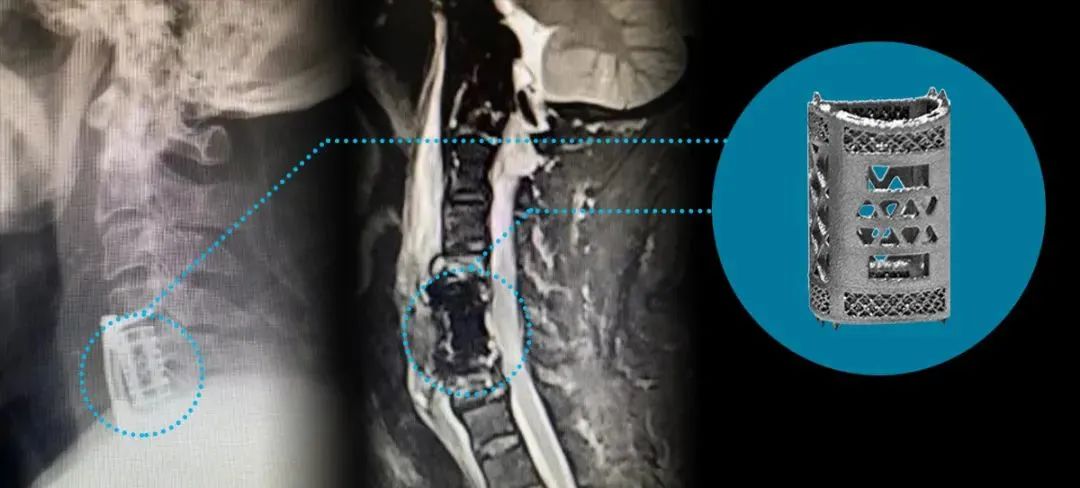

2022年9月,湘雅常德医院脊柱外科陈芳田主任团队成功完成一例颈椎间盘髓核切除术+C5椎体部分切除术+颈椎前路椎管减压术+脊髓神经根探查术+3D打印多孔型椎体融合器置入术。多孔型椎体融合器由湖南华翔医疗科技有限公司联合南华大学附属第一医院脊柱外科团队,采用华曙高科金属3D打印解决方案研发加工制造,获得三类医疗器械许可证的选区激光熔融技术(金属3D打印SLM技术)骨科植入假体产品。

经过科室讨论、与患者及家属沟通后,陈芳田主任团队采用湖南华翔医疗科技有限公司设计生产的3D打印多孔型椎体融合器为患者解决难题。

手术顺利完成,患者术后肢体肌力明显改善,疼痛麻木缓解。术后影像学检查显示:减压充分,融合器位置良好。患者对手术效果非常满意。

△患者术后影像学资料